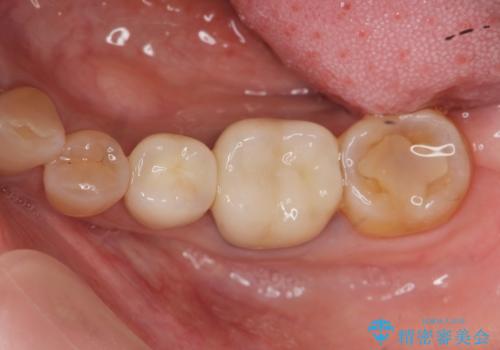

臼歯 咬合の再構成

- 20年前に治療した銀歯が壊れ、審美的な修復を希望され来院されました。

銀歯・虫歯を除去し、ジルコニアを咬合再構成を行います。

- 66万円(仮歯・ジルコニアクラウン×6)費用は治療当時の料金となります

ジルコニアクラウンは補綴治療を行う上で、審美的かつ強度を備えたクラウンです。